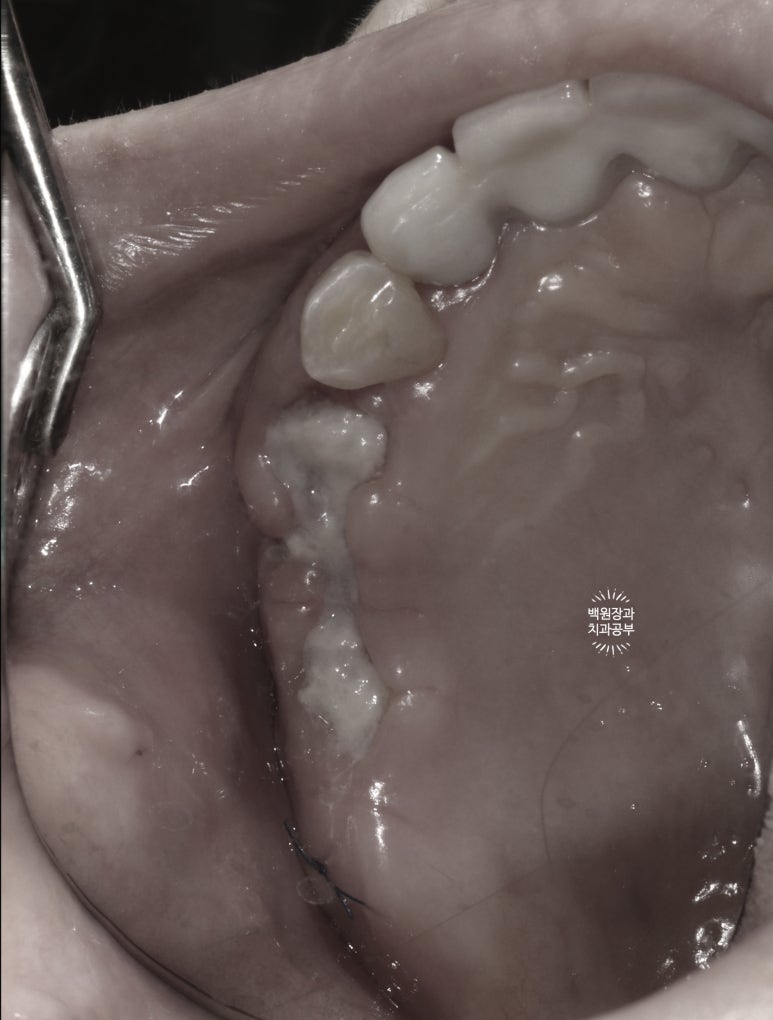

1주일이 지나 실밥을 제거한 뒤의 소견입니다.

아주 당연하지만, 이와 임플란트를 뽑으면 그 자리에 잇몸이 없으니 구멍이 나 있을 수 밖에 없겠죠?

그 구멍을 통해 뼈이식재가 다 쏟아진다면 우리가 했던 치조제보존술은 아무 의미가 없겠죠.

그래서 사용하는 것이 차폐막이라는 막이고, 실밥을 제거할 때 보이는 저 흰색의 재료들이 그 차폐막입니다.

차폐막은 콜라겐으로 이루어져 있고, 덴티움사의 차폐막이 cross-linked 방식으로 제조되어 잘 흡수되지 않고 오래 버텨주기로 유명합니다.

딱 봐도 뼈이식재가 삐져나오지 않고 잘 갇혀있을 것 같은 느낌이죠?